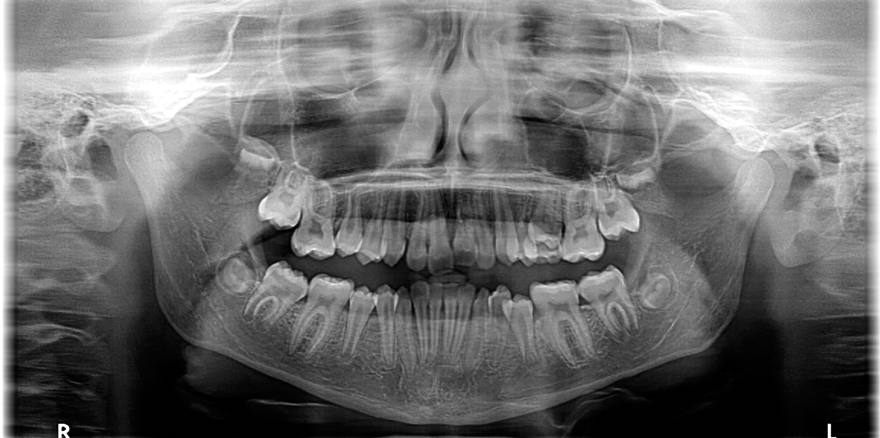

Fig 1. Patient was missing teeth Nos. 7 and 10 (Fig 1). Canine substitution was the treatment used to replace these missing teeth (Fig 2).

Figure 1

Fig 2. Patient was missing teeth Nos. 7 and 10 (Fig 1). Canine substitution was the treatment used to replace these missing teeth (Fig 2).

Figure 2

Canine substitution can be an excellent alternative for the replacement of the missing maxillary lateral incisor (Figure 1 and Figure 2). This treatment option can be particularly effective if the canine has a flat facial surface, is not too wide mesiodistally, and has a color similar to the contralateral lateral incisor. Patients with missing lateral incisors who present with maxillary dentoalveolar protrusion and/or an Angle class II molar relationship and minimal crowding in the mandibular arch are considered excellent candidates for canine substitution.7